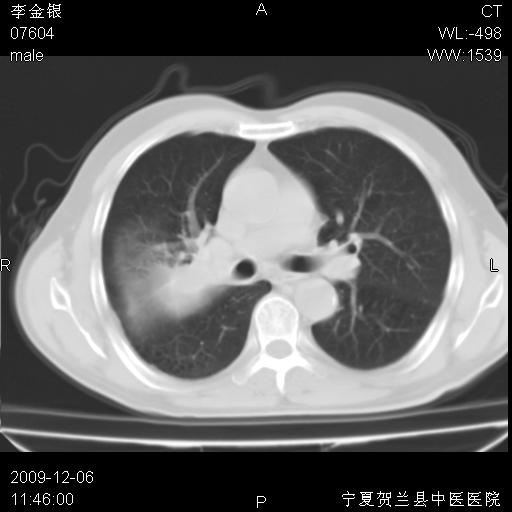

考虑右侧中央型肺癌并阻塞性炎症及不张,建议ct增强!!

符合中央型肺癌的ct表现并肺出血。但有一点腔静脉后有一钙化的淋巴结啊

右上叶支气管狭窄,管壁增厚,远端斑片状软组织影,病灶邻近叶间裂,叶间裂无移位。

诊断右肺中央型肺癌。

那个片影应该大部分都是病灶,病灶沿肺段支气管分支生长,后段完全显示不清、闭塞。若为不张应该伴有叶裂的移位,若为炎症应有空气支气管征。